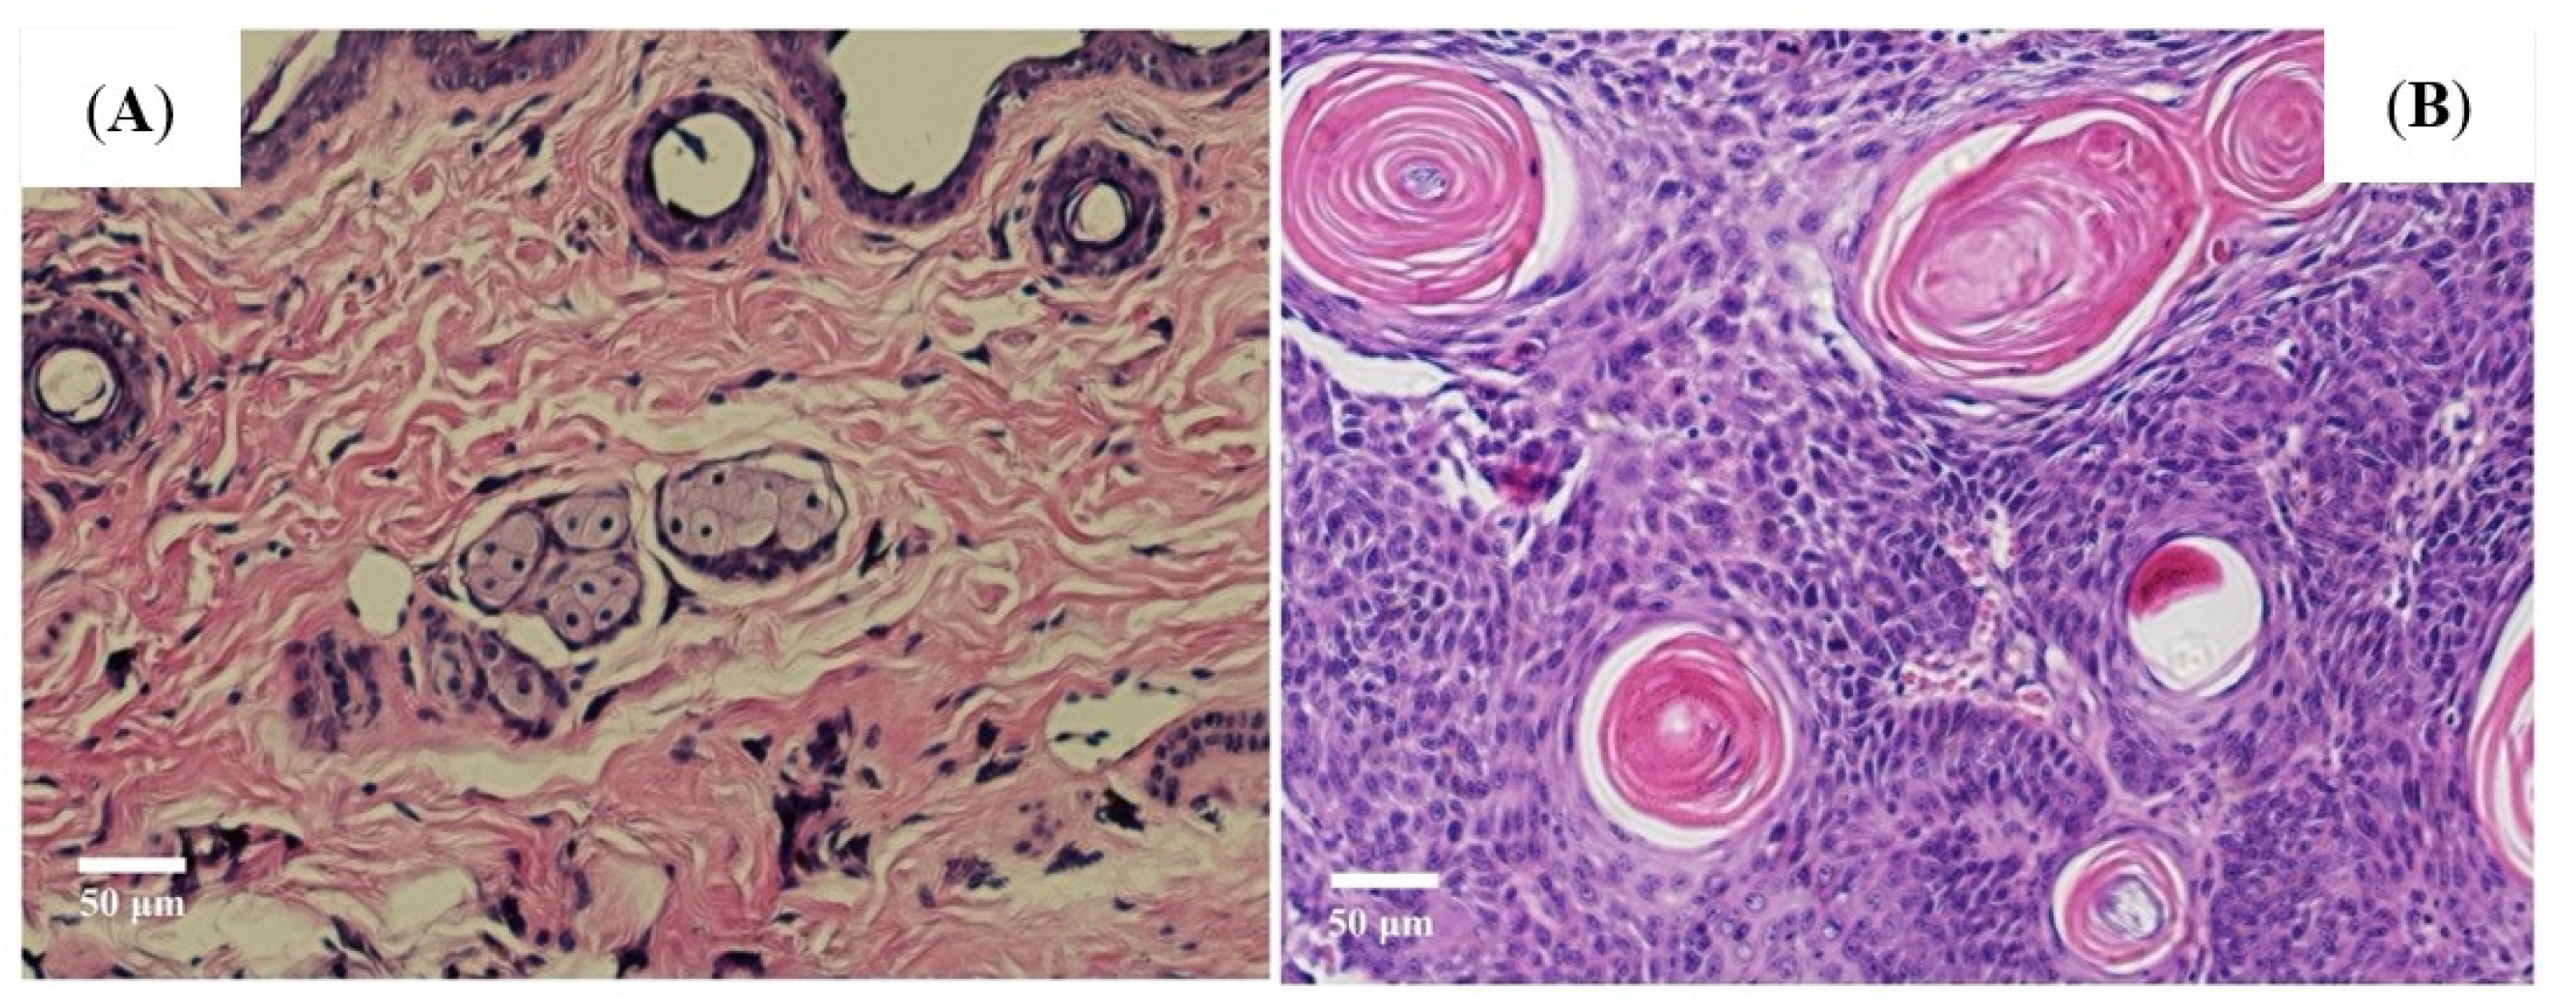

3.1. UVR Induced Skin Canceration in Pathology